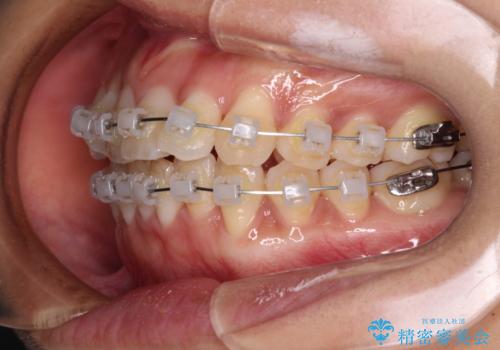

- クリアブラケット

- 1年6ヶ月

- 10-30回

日々前歯の捻れが解消されていくので、歯の動きを楽しみながら矯正治療を進めることができました。